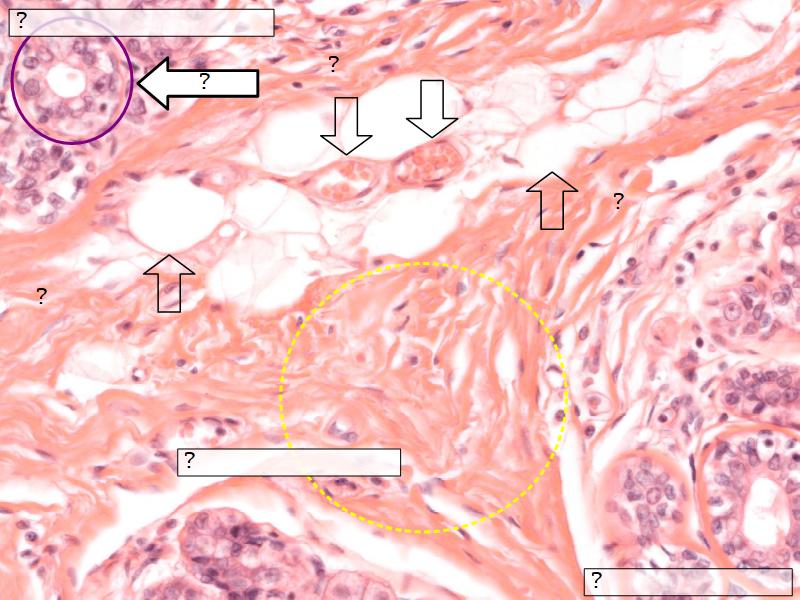

Morphology

What are the main morphological features of the nipple?

(4)

• Covered with skin

• Consists of dense collagenous connective tissue

• Interlaced with smooth muscle fibres

• Contains openings of lactiferous ducts

Skin

• Keratinized stratified squamous epithelium

• Sebaceous glands

Stroma

• Collagenous connective tissue

• Irregular dense connective tissue

• Smooth muscle

• Fibres and bundles

• Lactiferous sinusses

• Stratified cuboidal epithelium